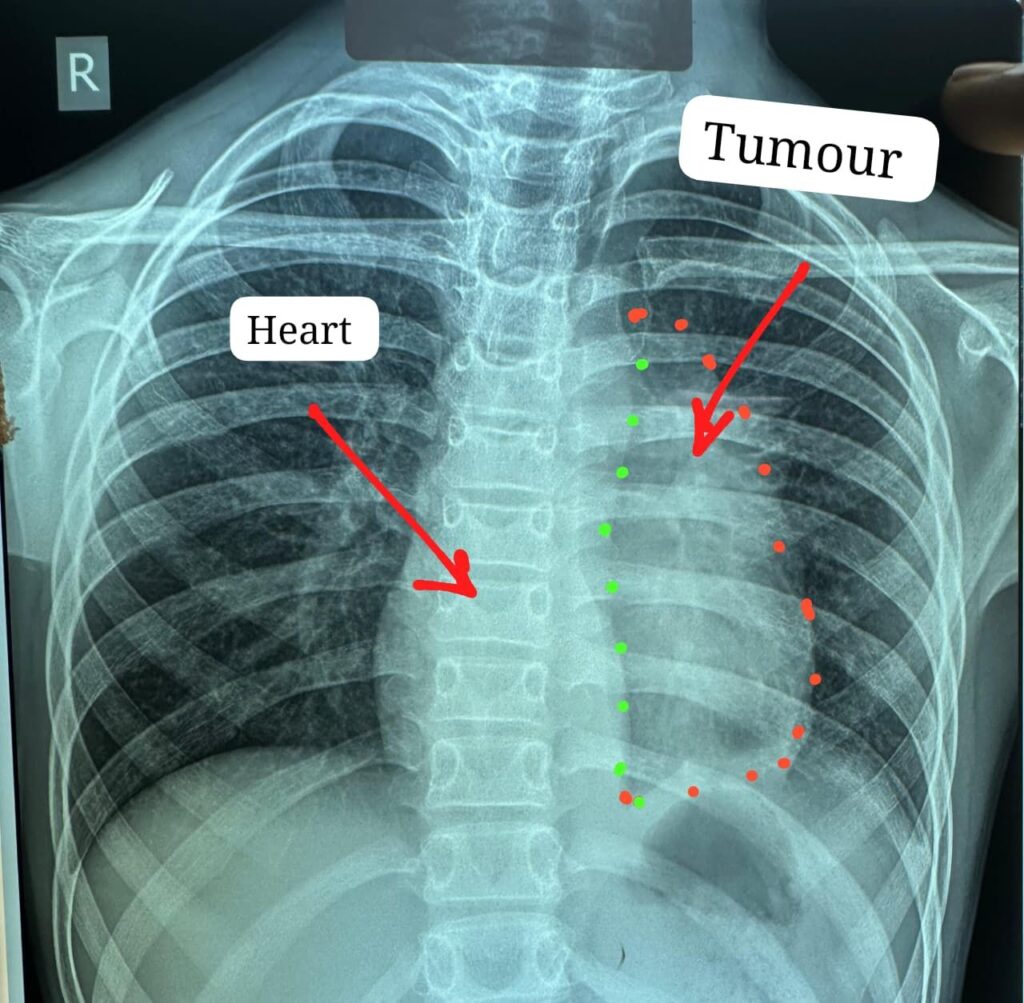

ट्यूमर ने हार्ट के साथ, पेरिकार्डियम, फ्रेनिक नर्व,महाधमनी, मुख्य पल्मोनरी आर्टरी(एमपीए), लेफ्ट एट्रियम एवं फेफड़े को अपनी चपेट में ले रखा था

डॉक्टरों के अनुसार यह ट्यूमर सामान्यतः 40 से 60 वर्ष के लोगों में पाया जाता है और बच्चों में इसका मिलना अत्यंत दुर्लभ है। यह ट्यूमर हृदय, पेरिकार्डियम, फ्रेनिक नर्व महाधमनी (एओर्टा), मुख्य पल्मोनरी आर्टरी, लेफ्ट एट्रियम और फेफड़े से चिपका हुआ था। ऐसे मामलों में ट्यूमर को पूरी तरह निकाल पाना (आर-0 रिसेक्शन) लगभग असंभव माना जाता है, लेकिन अस्पताल में उपलब्ध हार्ट-लंग मशीन की मदद से यह संभव हो पाया।